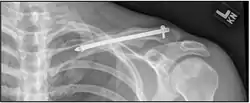

| شکستگی چند قطعهای ترقوه راست | |